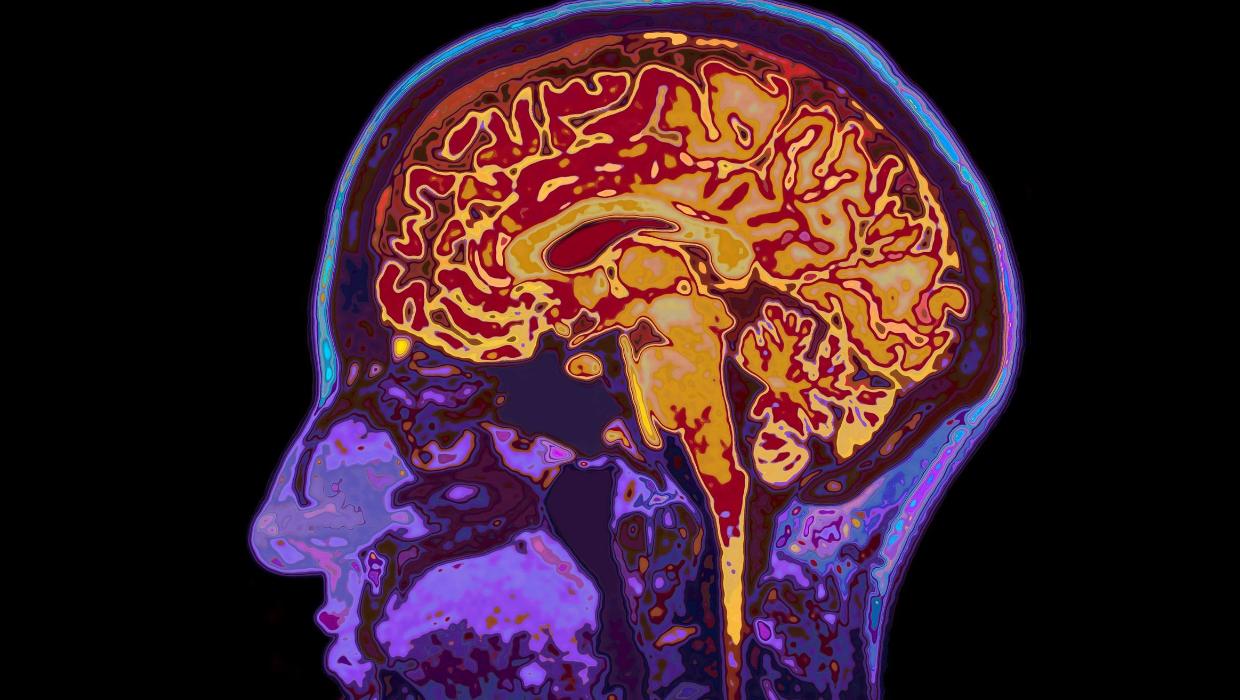

Research from the University of Cambridge has redefined our understanding of brain development, revealing that the human brain remains in a state of adolescence until the age of 32. This study, published in March 2024, identifies five significant epochs in brain maturation, along with four critical turning points throughout an individual’s life.

The research highlights the brain’s remarkable ability to adapt and change, emphasizing that mental development does not conclude in early adulthood, as previously thought. Instead, this study suggests that significant cognitive transformations continue into a person’s early thirties.

According to the study, the brain undergoes five major stages: early childhood, adolescence, young adulthood, middle age, and old age. Each stage is marked by notable shifts in cognitive function, emotional regulation, and decision-making processes. The authors of the study noted that the brain’s maturation is not just a matter of age but is influenced by experiences and environmental factors.

The study’s findings indicate that while individuals may reach physical maturity in their twenties, their brains are still evolving. This new perspective may influence how society approaches education, mental health, and even the legal age of responsibility.

In addition to extending the timeline for cognitive development, the research also establishes that aging begins at age 66. This finding refines our understanding of when cognitive decline may start, suggesting that individuals may experience a more gradual transition into this phase of life than previously recognized.